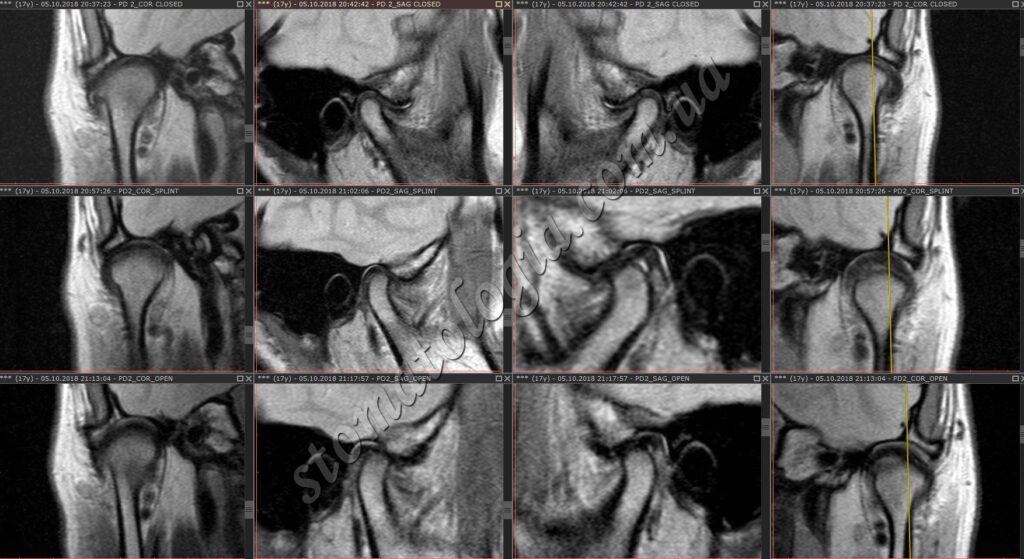

Фото 4-5. Завдяки знімкам можна оцінити положення суглобового диска та правильно виставити нижню щелепу. МРТ-дослідження проводиться на етапі діагностики

Це дозволяє точніше оцінити стан диска у випадках, коли «клацає» щелепа, якщо у вас є відчуття «скутості» під час їжі, говоріння або якщо ви помічали, що щелепу «заклинювало».